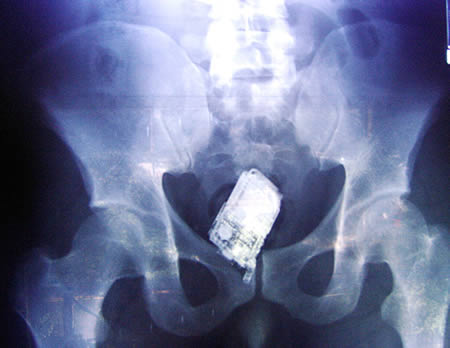

お尻は日本でもたまーに救急に来るで

中国率高すぎるだろ

ストレートのバイブは尻に入れたら抜けなくなるのか。

尻に異物が入る時はだいたい「転んだ拍子に」って言うけど医療関係者はそんな与太話は誰も信じてないだろうね。

5・13・17は性的な目的で入れたんだろうな

それを正直に言えなくてこういう訳の分からん説明をする人は良く居る

医者からすれば一目瞭然だし普通に○ナニーしてましたっていえばいいのにな